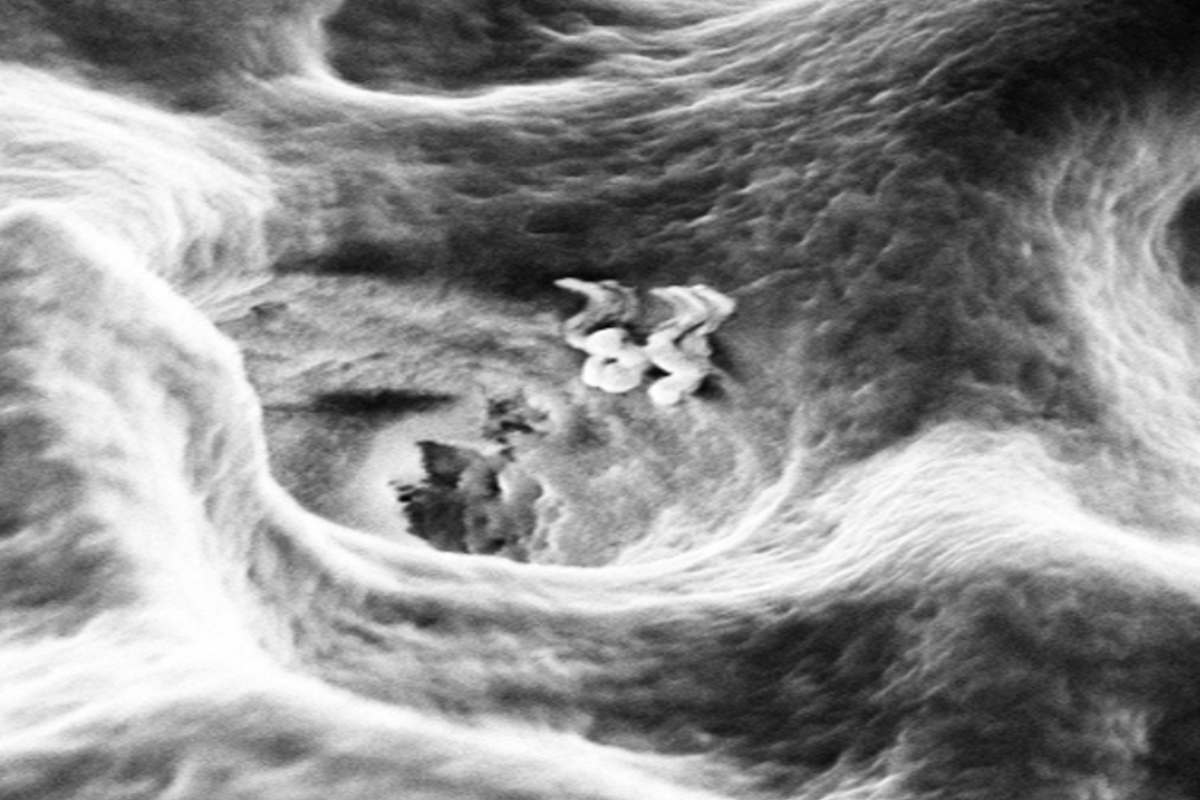

IISc Bengaluru develops nanobots that can enter a dentinal tubule. (Supplied)

The study shows that the nanobots’ movement into extracted tooth samples could be tracked using a microscope.

By tweaking the magnetic field frequency, the researchers could make the nanobots move at will and penetrate deep inside the dentinal tubules.